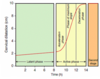

What do you see here? What do you want to do?

- FHR w/baseline of 170 bpm, minimal variability

-

Late deceleration: following contraction, slight downward trend of FHR, then slope upward

1. Indication that fetus might be becoming hypoxic and acidemic

2. Indication for expedited cesarean delivery to get baby out as soon as possible